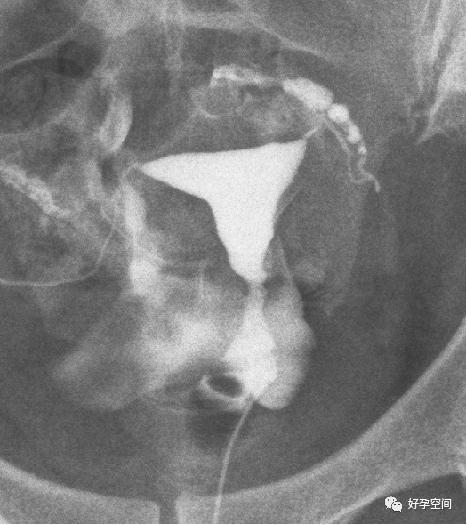

右侧输卵管伞部粘连,左侧输卵管壶腹部扭曲

弥散相,双侧输卵管内见造影剂残留影,盆腔内片状造影剂聚集(提示盆腔粘连)